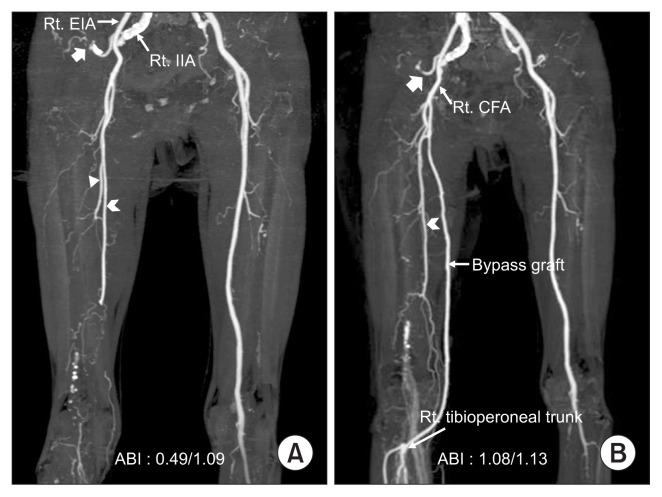

A 71-year-old woman presented with an enlarging mass in the right buttock, with pain and tingling sensation in sitting position. Five years ago, she was diagnosed with acute limb ischemia due to acute thrombosis of right persistent sciatic artery (PSA), and she underwent successful thromboembolectomy and femoro-tibioperoneal trunk bypass. Computed tomography angiography revealed a huge PSA aneurysm (PSAA). During the previous bypass, the distal popliteal artery was ligated just above the distal anastomosis to exclude the PSAA, whose proximal end was already thrombosed. However, PSAA has grown to cause compression symptoms, and the mechanism of aneurysm growth can be ascribed to type 1a or type 2 endoleak. In order to relieve the compression symptoms, aneurysm excision was performed without any injury to the sciatic nerve. A postoperative tingling sensation due to sciatic-nerve stimulation in the supine position resolved spontaneously one month after surgery.

一名71岁女性因右臀部肿物增大伴坐位时疼痛和刺痛感就诊。5年前,她因右侧坐骨动脉(PSA)急性血栓形成导致急性肢体缺血,接受了成功的血栓切除术和股-胫腓干旁路移植术。计算机断层血管造影显示巨大的PSA动脉瘤(PSAA)。在之前的旁路手术中,腘动脉远端在远端吻合口上方结扎以排除PSAA,其近端已形成血栓。然而,PSAA增大导致压迫症状,动脉瘤生长机制可归因于1a型或2型内漏。为缓解压迫症状,在未损伤坐骨神经的情况下进行了动脉瘤切除术。术后因仰卧位坐骨神经刺激引起的刺痛感在术后1个月自发缓解。